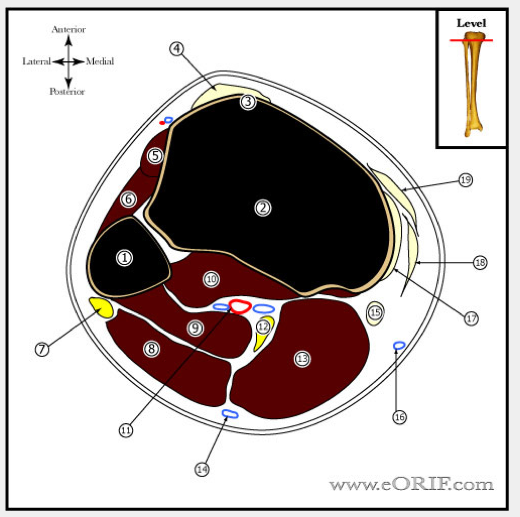

NAME THE ANATOMICAL STRUCTURES

Name the structures

name the structures

- Cephalic vein

- FCR

- FDS

- ulnar artery

- ulnar nerve

- FCU

- FDP

- basilic vein

- ulnar shaft

- APL

- PIN

- ECU

- EDM

- Supinator

- FPL

- Radial shaft

- deep branch of radial nerve

- EDC

- ECRB

- ECRL

- BR

- Superficial radial nerve

- PT

- radial artery

- median nerve

- volar (flexors)

- Dorsal (extensors)

- mobile wad